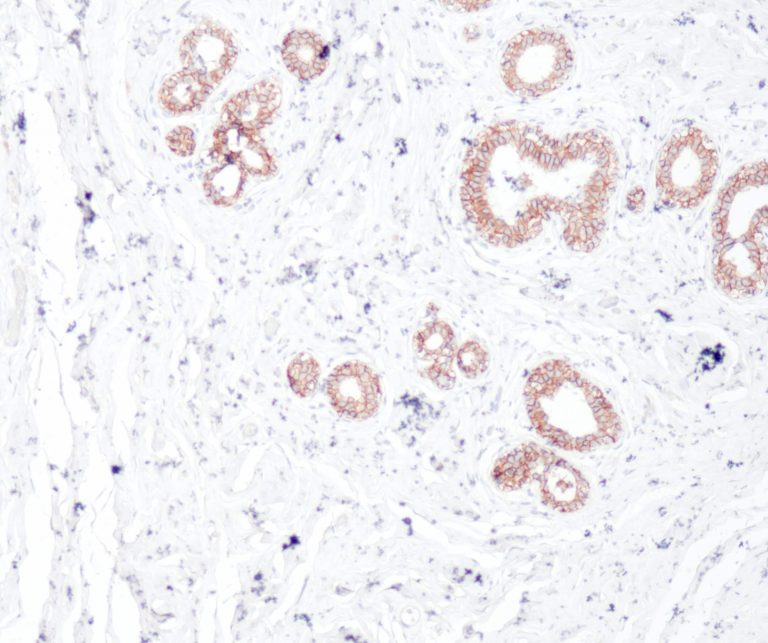

Vascular Pathology

Gastrointestinal (GI) Pathology

General Marker

Breast Pathology

Endocrine Pathology

Gynecological Pathology

Neuropathology

Infection Markers

Lung Pathology

Urinary Tract Pathology

Transplantation Pathology

Soft Tissue Pathology

Hematopathology